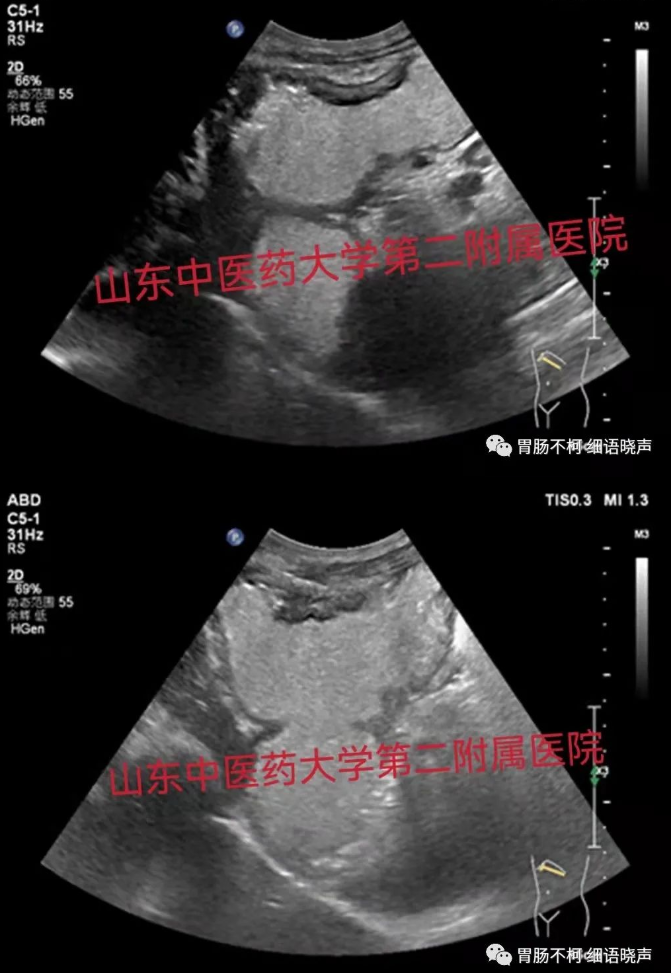

病例四,胃窦壁弥漫性增厚,层次不清晰:

病例五,以胃壁固有层增厚为主的胃壁增厚性病变: